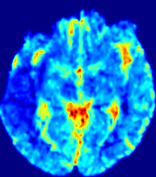

4.3.2 Diffusion Imaging via Advection-Diffusion

Slice #1Slice #2Slice #3Slice #4Slice #5Slice #6Dgtsuperscript𝐷gtD^{\text{gt}}Refer to captionRefer to captionRefer to captionRefer to captionRefer to captionRefer to captionDestsuperscript𝐷estD^{\text{est}}Refer to captionRefer to captionRefer to captionRefer to captionRefer to captionRefer to captionRefer to caption0.300.300.300.240.240.240.180.180.180.120.120.120.060.060.060.000.000.00(mm2/s)𝑚superscript𝑚2𝑠(mm^{2}/s)𝐕est𝟐subscriptnormsuperscript𝐕est2\|\bf{V}^{\text{est}}\|_{2}Refer to captionRefer to captionRefer to captionRefer to captionRefer to captionRefer to captionRefer to caption0.00300.00300.00300.00240.00240.00240.00180.00180.00180.00120.00120.00120.00060.00060.00060.00000.00000.0000(mm/s)𝑚𝑚𝑠(mm/s)

Figure 15: PIANO identifiability testing: diffusion imaging via advection-diffusion. Top row shows Dgtsuperscript𝐷gtD^{\text{gt}} used for simulating ground truth pure diffusion. Rows below show the estimated Destsuperscript𝐷estD^{\text{est}} and 𝐕est2subscriptnormsuperscript𝐕est2\|{\bf{V}}^{\text{est}}\|_{2} on corresponding slices. Note that the plotted value scale for 𝐕est2subscriptnormsuperscript𝐕est2\|{\bf{V}}^{\text{est}}\|_{2} is 0.01 of that for Dgtsuperscript𝐷gtD^{\text{gt}} and Destsuperscript𝐷estD^{\text{est}}.

Similarly, we test the behavior of PIANO when estimating both advection and diffusion from a pure diffusion-driven process. The goal is to determine if PIANO is able to recognize that there is only diffusion governing the given concentration time-series. We use the same ‘Diffusion Imaging’ data simulation of Sec. 4.2.1 as the concentration dataset, PIANO estimates both velocity 𝐕estsuperscript𝐕est{\bf{V}}^{\text{est}} and diffusivity Destsuperscript𝐷estD^{\text{est}}. Estimation results in Fig. 15 confirm PIANO’s identifiability again: the estimated 𝐕est2subscriptnormsuperscript𝐕est2\|{\bf{V}}^{\text{est}}\|_{2} is almost invisible compared to Destsuperscript𝐷estD^{\text{est}}, even plotted with a 1%percent11\% value range compared to that for Destsuperscript𝐷estD^{\text{est}}. On the other hand, Destsuperscript𝐷estD^{\text{est}} achieves comparable estimation performance as ‘Diffusion Imaging via Diffusion’ in which PIANO predicts Destsuperscript𝐷estD^{\text{est}} alone (shown in Fig. 13).